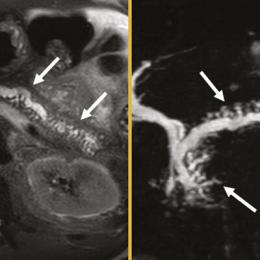

Cystite emphysémateuse

Une patiente de 89 ans, sans antécédent majeur, consulte aux urgences à la suite d’une chute accidentelle avec fracture...